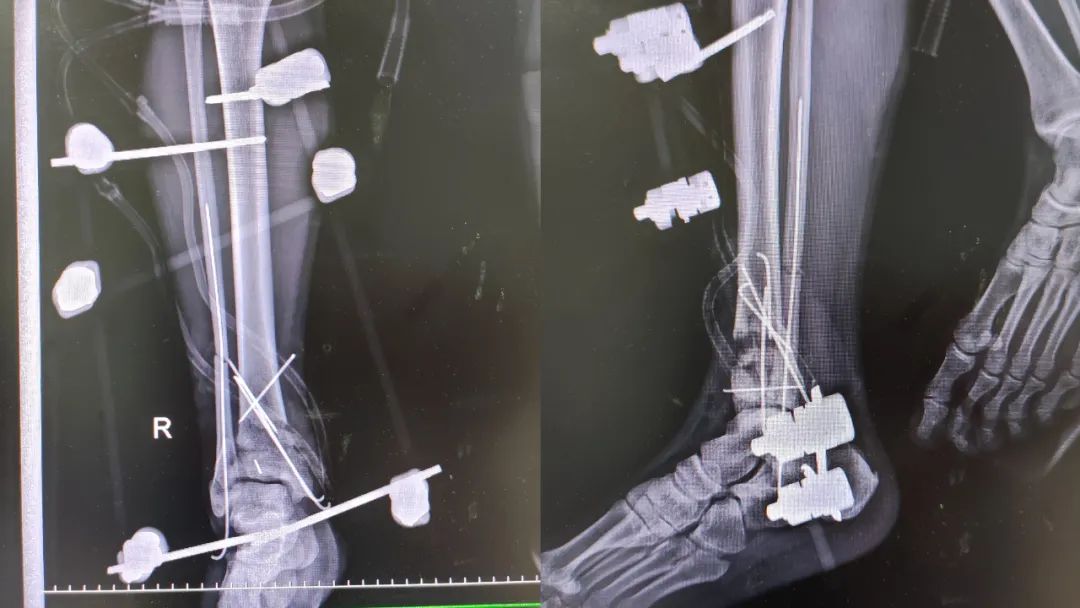

在腰硬联合麻醉、基础麻醉下行「右踝关节开放性骨折扩创探查骨折复位外固定架固定、VSD 负压引流术」,经过紧张有序的手术,患者安返病房。

外固定支架是应用固定针经皮穿入骨折端周围,并用各种形态的连接杆将固定针结合在一起的骨固定器械,有微创、可调节的特点。

外固定支架的优点:可以用于开放性骨折对骨折再次复位及固定,对骨血运破坏较小,对骨折软组织覆盖影响小。在感染风险高或者已有感染情况下可以降低感染的风险。